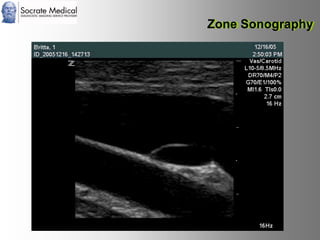

Il documento presenta la tecnologia della zone sonography, che promette una rivoluzione nel campo degli ultrasuoni, superando i limiti dei sistemi tradizionali grazie a metodi di acquisizione dati più veloci e una gestione delle informazioni migliorata. Questa tecnologia consente una maggiore definizione dell'immagine, una riduzione degli artefatti e un'ottimizzazione del processo diagnostico, con vantaggi in termini di tempo e costi. Inoltre, il channel domain processing e la zone speed technology offrono applicazioni avanzate e miglioramenti nella sicurezza diagnostica.